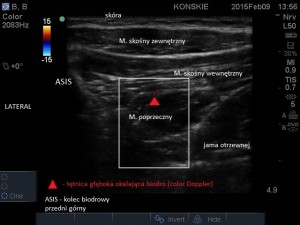

W celu lokalizacji nerwów liniową głowicę USG przykładamy w linii łączącej grzebień kości biodrowej z pępkiem (ok. 5 cm dogłowowo i grzbietowo w stosunku do kolca biodrowego przedniego górnego -ASIS), następnie lokalizujemy trzy warstwy mięśni, kolejno idąc od góry: mięsień skośny zewnętrzny, wewnętrzny oraz poprzeczny. Nerwy IiN i IhN na tym poziomie przebiegają w przestrzeni TAP i w obrazie ultrasonograficznym przybierają postać okrągłych hipoechogenicznych struktur. W pobliżu nerwów, w tej samej przestrzeni powięziowej, przebiega tętnica głęboka okalająca biodro, która może być przydatna w celu ich lokalizacji. Można ją odnaleźć używając opcji color Doppler.

- Tętnica głęboka okalająca biodro (color Doppler)